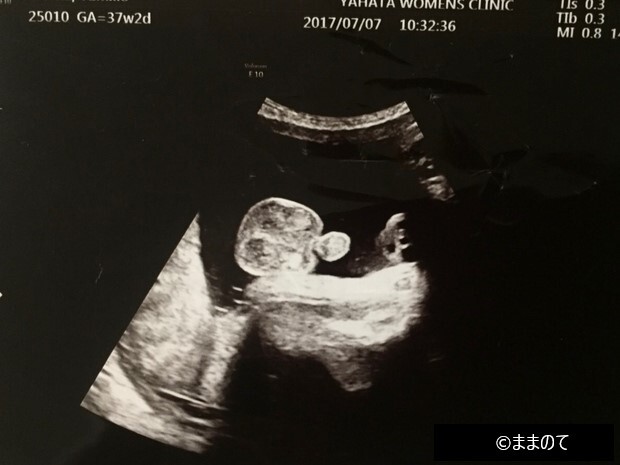

【男の子のエコー】妊娠36週

臨月に入ったころの赤ちゃんの外性器です。男の子のシンボルがはっきりと確認できますね。いつ生まれてきてもおかしくないほどに成長している姿が垣間見れて、生まれてくるのが待ち遠しくなりそうです。